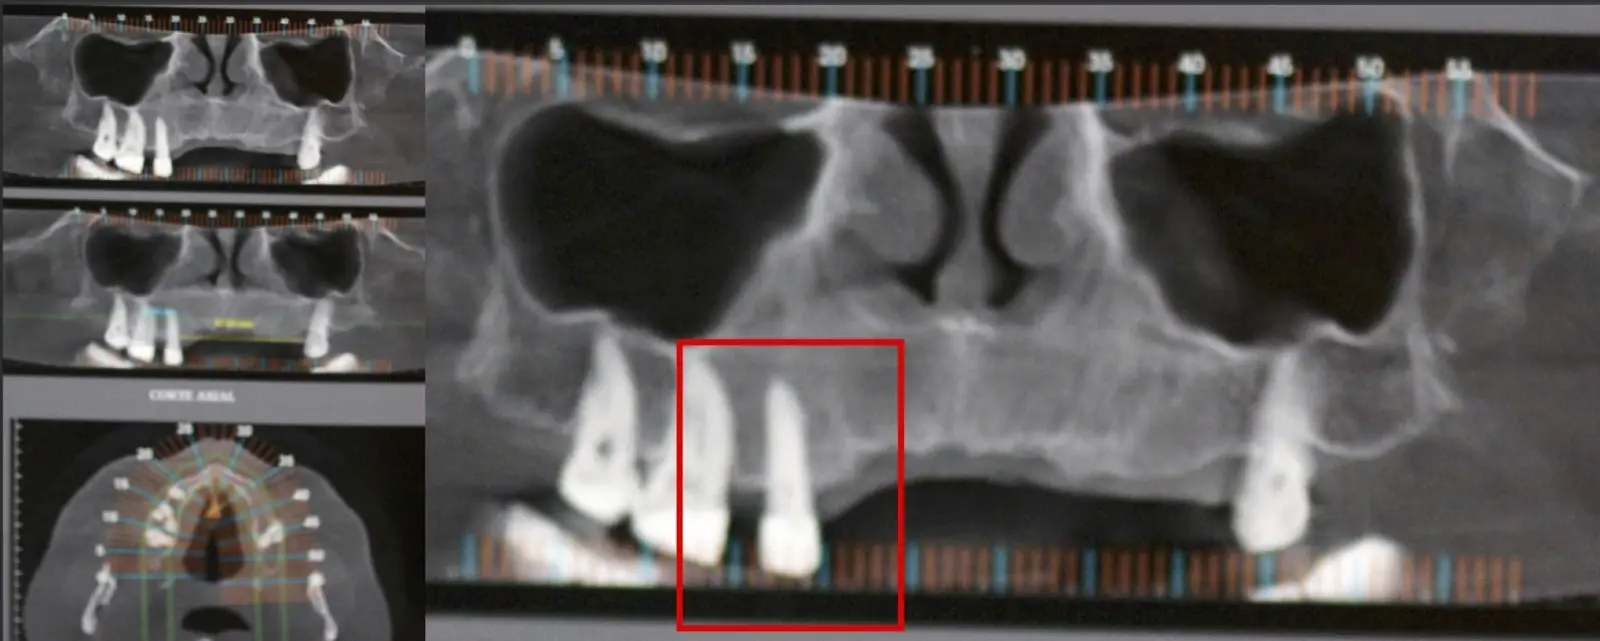

Los tratamientos endodónticos tienen una predictibilidad de éxito variable (20-90%).1 Sin embargo y con cierta frecuencia (15%), pueden aparecer complicaciones a nivel apical2 posterior al tratamiento, o incluso cuando la pieza ya posee la restauración protésica definitiva.3 Estos escenarios no deseados pueden presentarse con sintomatología persistente o esporádica y estar acompañados de imágenes radiolúcidas/hipodensas apicales.

El origen puede ser bacteriano (colonias bacterianas persistentes4, patología periodontal asociada5, reinfecciones por falta de sellado coronal), mecánico (preparación deficiente, fractura de instrumentos, fracturas radiculares6, extravasación de material de obturación7 con ó sin compromiso de estructuras vecinas) y anatómico (conductos accesorios poco permeables o calcificados)8 (Figuras 1 - 4).

La microcirugía endodóntica apical busca conservar la mayor cantidad de longitud de raíz y de hueso circundante sano para no afectar la estabilidad de la pieza.11 Por ello, es ideal el uso de microscopios, elementos de magnificación, instrumental específico (insertos de ultrasonido endodónticos) y materiales de sellado eficientes para el tratamiento retrogrado. Su éxito es alto y evidencia una cicatrización ósea completa en el 74% de los casos al año de tratamiento.12 Cabe destacar que este logro está asociado también, a predictores propios de cada paciente, como la edad, tipo de pieza, profundidad de sondaje y extensión de la lesión.1 El uso complementario de la tomografía computarizada es resaltante como el instrumento imagenológico de elección para la etapa de planificación microquirúrgica,13 ya sea para una ejecución a mano alzada o con guías prefabricadas.14,15